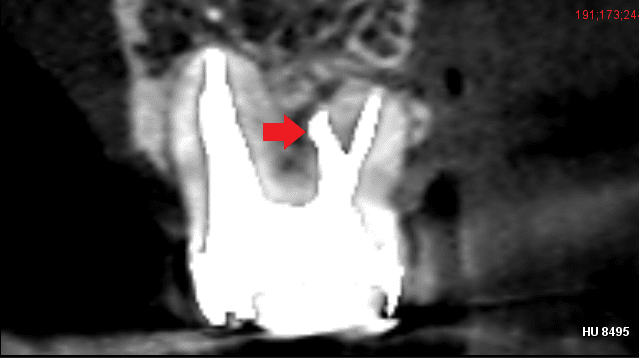

下の画像は、破折ファイルが根管を塞ぎ膿の治療を阻んでいるケースです。CT画像で歯根の先に膿の影がみられますが、破折ファイルが根管を塞いでいるため、このままでは再根管治療によって根管に残る細菌感染を除去し膿を改善することができません。根管治療によって歯を残すために、まさに破折ファイル除去が必要なケースです。(但し、根の周りに膿などの病変がなく根管内に細菌感染が無いことが考えられる場合は、破折ファイルは除去しなくても良いことがあります)